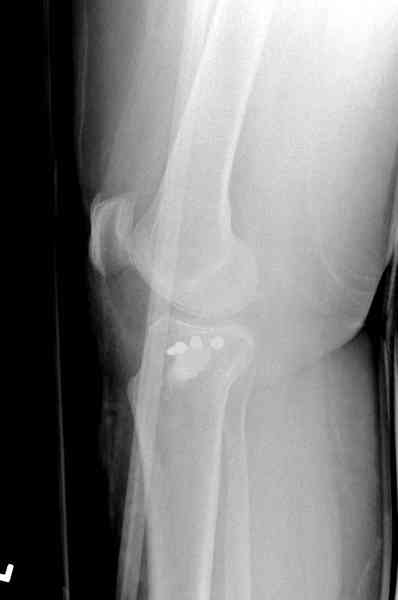

Медиально, обычно на протовоположной

строне, делается окно в кортикальном слое, кривым забойником под рентгеном поднимается импрессия.

Это техника применяется, когда имеется

центральная импрессия, а при ипрессии с краевым переломом - после приподнимания импрессии опорная (Butress) пластина, как на снимке.